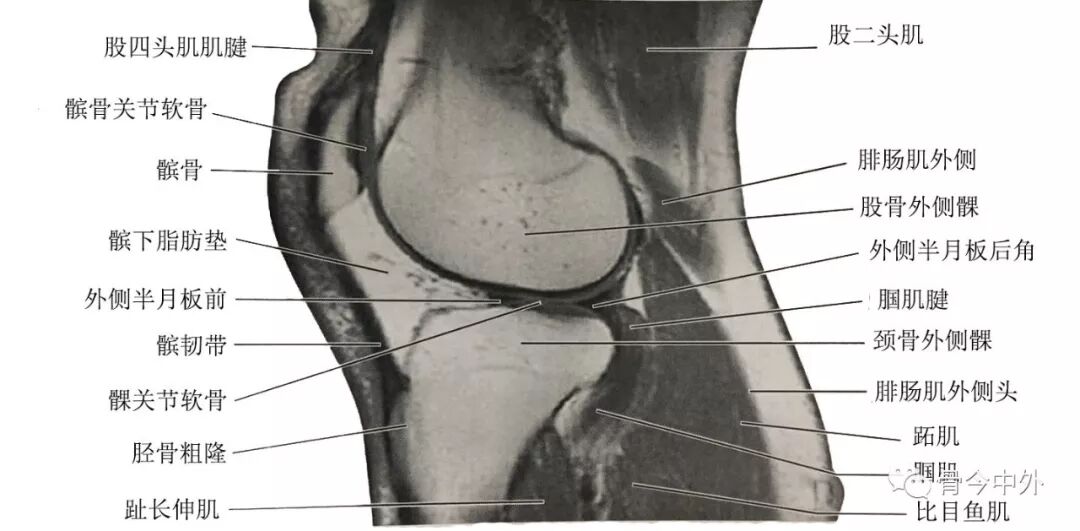

(2)膝正中矢状断层:该层面解剖关系结构如图

膝正中矢状断层